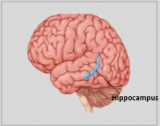

A neuroanatomia é o ramo da anatomia que estuda a anatomia do sistema nervoso, ou seja, a estrutura, a função e a organização do sistema nervoso. O sistema nervoso é um dos sistemas mais complexos do corpo humano e inclui o cérebro, a espinal medula, os nervos periféricos e os gânglios nervosos. A neuroanatomia preocupa-se com a forma como estas estruturas estão ligadas entre si, como os sinais são transmitidos entre as células nervosas e como as diferentes partes do sistema nervoso trabalham em conjunto para controlar as funções corporais e cognitivas. Os neuroanatomistas utilizam técnicas de imagiologia avançadas, como a ressonância magnética (MRI), a tomografia por emissão de positrões (PET) e a microscopia para visualizar as estruturas e funções do sistema nervoso.